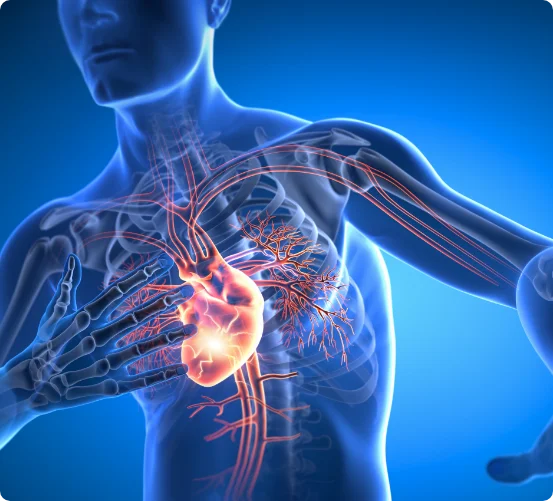

Atrial fibrillation is a type of arrhythmia (abnormal heart rhythm) where the upper chambers of the heart (the atria) beat irregularly and often rapidly. Instead of contracting in a coordinated way, the atria “quiver,” which can lead to inefficient blood flow, an increased risk of stroke, and symptoms like palpitations or fatigue.

Your heart has four chambers—two atria (upper) and two ventricles (lower). Normally, electrical impulses begin in the sinoatrial (SA) node, the heart’s natural pacemaker, prompting a steady, coordinated heartbeat.

In atrial fibrillation, this electrical system becomes disorganised, causing the atria to beat chaotically. This disrupts the normal flow of blood and can lead to blood pooling, increasing the risk of clot formation and stroke.